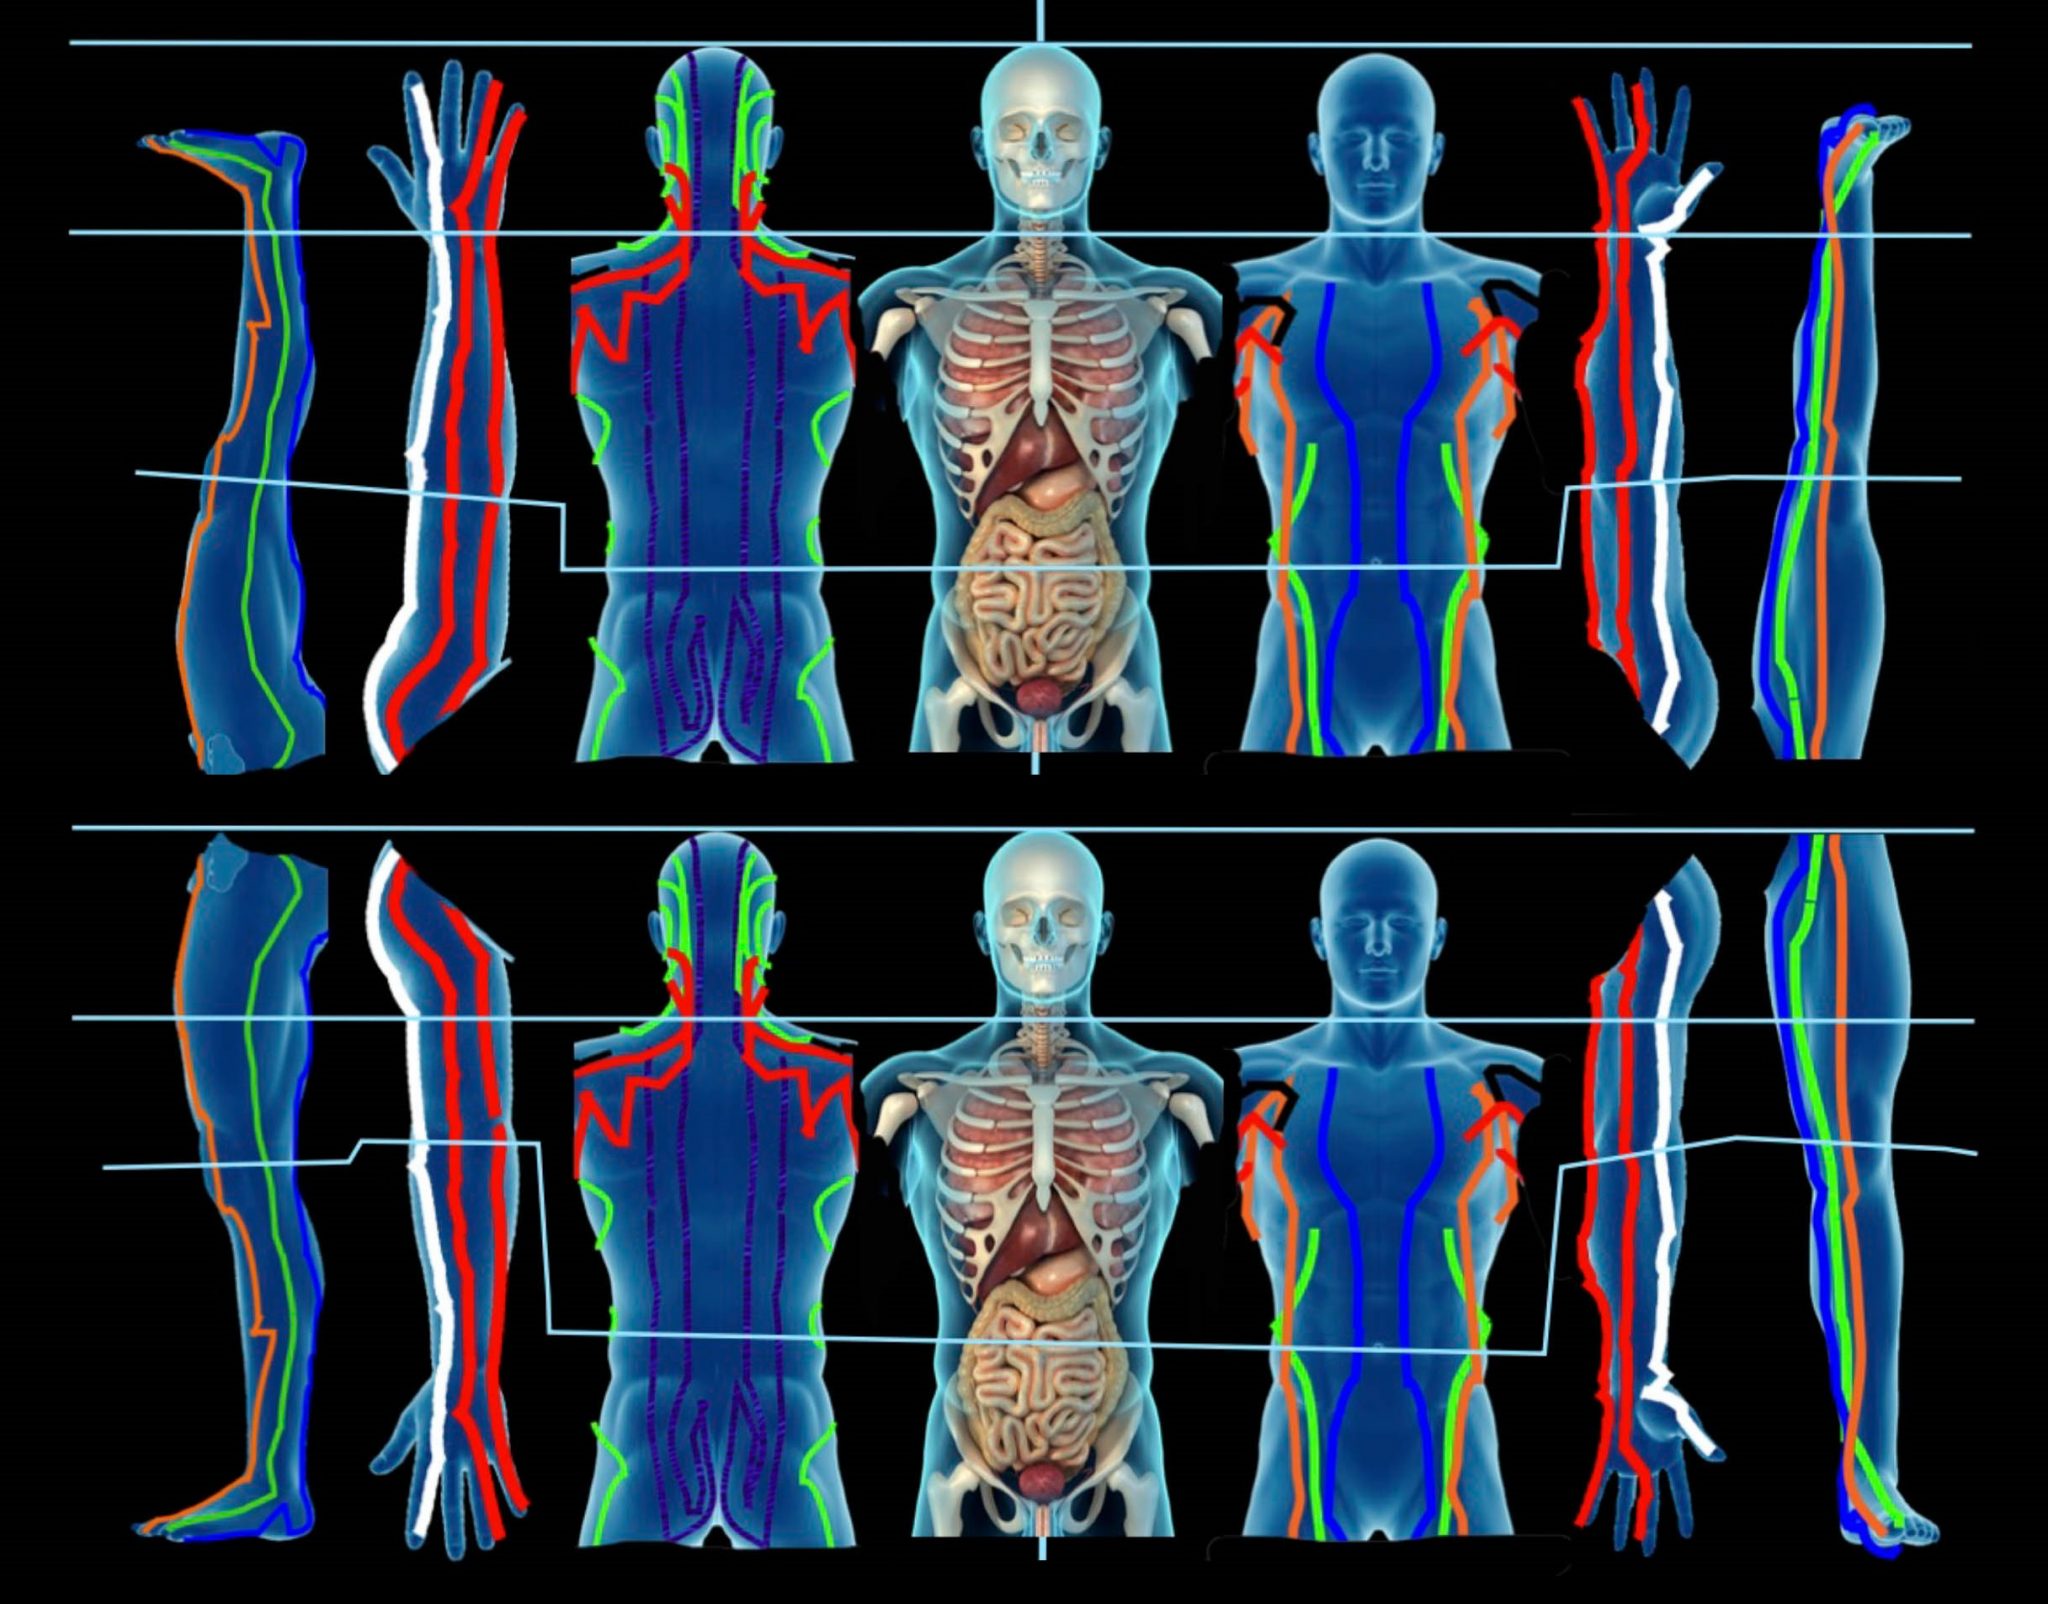

Rintanarsi nel proprio mondo virtuale diventa allora una vera postura, diventata una vera e propria sindrome: “Text Neck” o “cervicalgia da smartphone ” .

Con questo nome si identifica una sindrome dovuta ad un’errata postura nell’uso di apparecchi elettronici, che causa dolore e infiammazione a carico del collo, delle spalle, delle zone cervicale e toracica della colonna vertebrale, ipertrofia ed ipotrofia dei muscoli del collo, fino a modifica delle curve vertebrali, scompensi posturali e disfunzioni neurologiche.

La postura che, spesso, si assume nel guardare gli schermi di tablet, telefoni e computer porta la testa fuori dal suo asse naturale per molto tempo, andando a caricare le strutture con un peso fino a 5 volte maggiore del carico ordinario : la testa in posizione naturale pesa circa 5kg, inclinata di 60° arriva a pesarne 27.

Un carico di questo tipo, prolungato per molto tempo, può portare ad un eccessivo lavoro in contrazione ed estensione dei muscoli del collo, mentre tutto il corpo cerca di adattarsi per sostenere una visione frontale.

Localmente, tendono ad essere allungati ed indeboliti:

Questi muscoli, costituiti dai muscoli lungo del collo e lungo della testa, si trovano lungo la parte anteriore del rachide cervicale e aiutano a stabilizzare il collo. Quando si indeboliscono, i flessori cervicali profondi si allungano mentre il mento si inclina allontanandosi dal collo.

Questi sono muscoli estensori attaccati alla parte posteriore del rachide cervicale inferiore e alla colonna vertebrale toracica superiore. Svolgono un ruolo chiave nel ruotare e raddrizzare la colonna vertebrale. Quando i muscoli della spina dorsale si allungano e perdono forza, perdono la capacità di tenere dritti collo e schiena.

Trapezio medio e muscoli romboidi nella parte superiore della schiena portano le scapole all’indietro per mantenere le spalle ed il petto in una postura corretta. Trapezio e muscoli romboidi indeboliti permettono alle scapole di inclinarsi anteriormente, contribuendo ulteriormente a spalle curve e ad una postura della testa in avanti.

Localmente, tendono ad essere accorciati e contratti:

Queste quattro paia di piccoli muscoli, che collegano la parte bassa del cranio alla parte superiore delle cervicali, aiutano nella rotazione e nell’estensione della testa. Questi muscoli sono costantemente coinvolti nel mantenere la testa inclinata verso l’alto per guardare frontalmente.

Poiché i muscoli nella parte superiore della schiena tendono ad allungarsi perchè le spalle sono spostate in avanti, i muscoli pettorali possono accorciarsi e contrarsi. Potrebbero, per esempio, essere contratti i pettorali minori.

Questa coppia di muscoli si trova lungo la schiena e i lati del collo, viaggiando dalla colonna cervicale superiore fino alla scapola (scapola). La scapola levatrice svolge un ruolo chiave nel sollevare o elevare la scapola, oltre ad aiutare nei vari movimenti del collo. Se la scapola inizia a inclinarsi in avanti e a ruotare verso l’alto con spalle arrotondate, i muscoli scapole del levatore possono accorciarsi.

Generalmente la sindrome da Text Neck prevede uno o più sintomi tra cui:

Oltre che alla sindrome dolorosa, un prolungato stato di postura da Text Neck, può portare ad una degenerazione della lordosi cervicale (la “curva” a “C” che le vertebre cervicali formano naturalmente) che rischia di raddrizzarsi.

Uno degli effetti di una cattiva postura, come quella derivante dalla Text Neck, è il coinvolgimento di strutture anche distanti e a cui, nell’immediato, non si pensa.

Per esempio, uno spostamento in avanti della testa porterà ad uno spostamento del baricentro del corpo, con una conseguente variazione a livello del bacino e, conseguentemente, delle gambe..

Nel lungo periodo, quindi, si potrebbe avere sintomi non apparentemente collegati alla cervicalgia, ma derivanti dalla stessa postura che ne è la causa.

Questo aspetto del coinvolgimento a distanza e indiretto è intrinseco nel trattamento Shiatsu, qualsiasi stile si pratichi.

Da un punto di vista legato alla medicina tradizionale cinese, la cervicalgia da smartphone interessa principalmente il percorso dei meridiani di Vescica e Stomaco e i loro corrispettivi meridiani tendino-muscolari. C’è poi un aspetto legato al movimento Legno, che governa muscoli e tendini, e quindi i meridiani di Fegato e Vescica Biliare. Nei singoli casi, potrà esserci un coinvolgimento dei meridiani correlati : Intesino Tenue, Intestino Crasso, Polmone, Ministro del Cuore.

Il meridiano di Vescica, con il suo importante compito di tenere la “retta via” e la corretta postura risulta fondamentale. Nel trattamento si porrà attenzione alla zona cervicale: il cardine per “cambiare punto di vista” e quindi poter cambiare direzione.

Il meridiano di Stomaco è legato alla posizione “centrata”, quindi forte è il legame con il baricentro del corpo : l’addome ed il bacino. Il trattamento della parte finale del meridiano dal ginocchio al piede, coinvolge punti, come ST38, legati al trattamento delle spalle.

Questo collegamento tra la zona tibiale e le spalle risulta più facilmente comprensibile attraverso il bilanciamento reso famoso dal Dr. Richard Tan, che ha ripreso e sintetizzato quanto presente nella tradizione: una visione del corpo in cui braccia e gambe sono un riflesso del tronco.